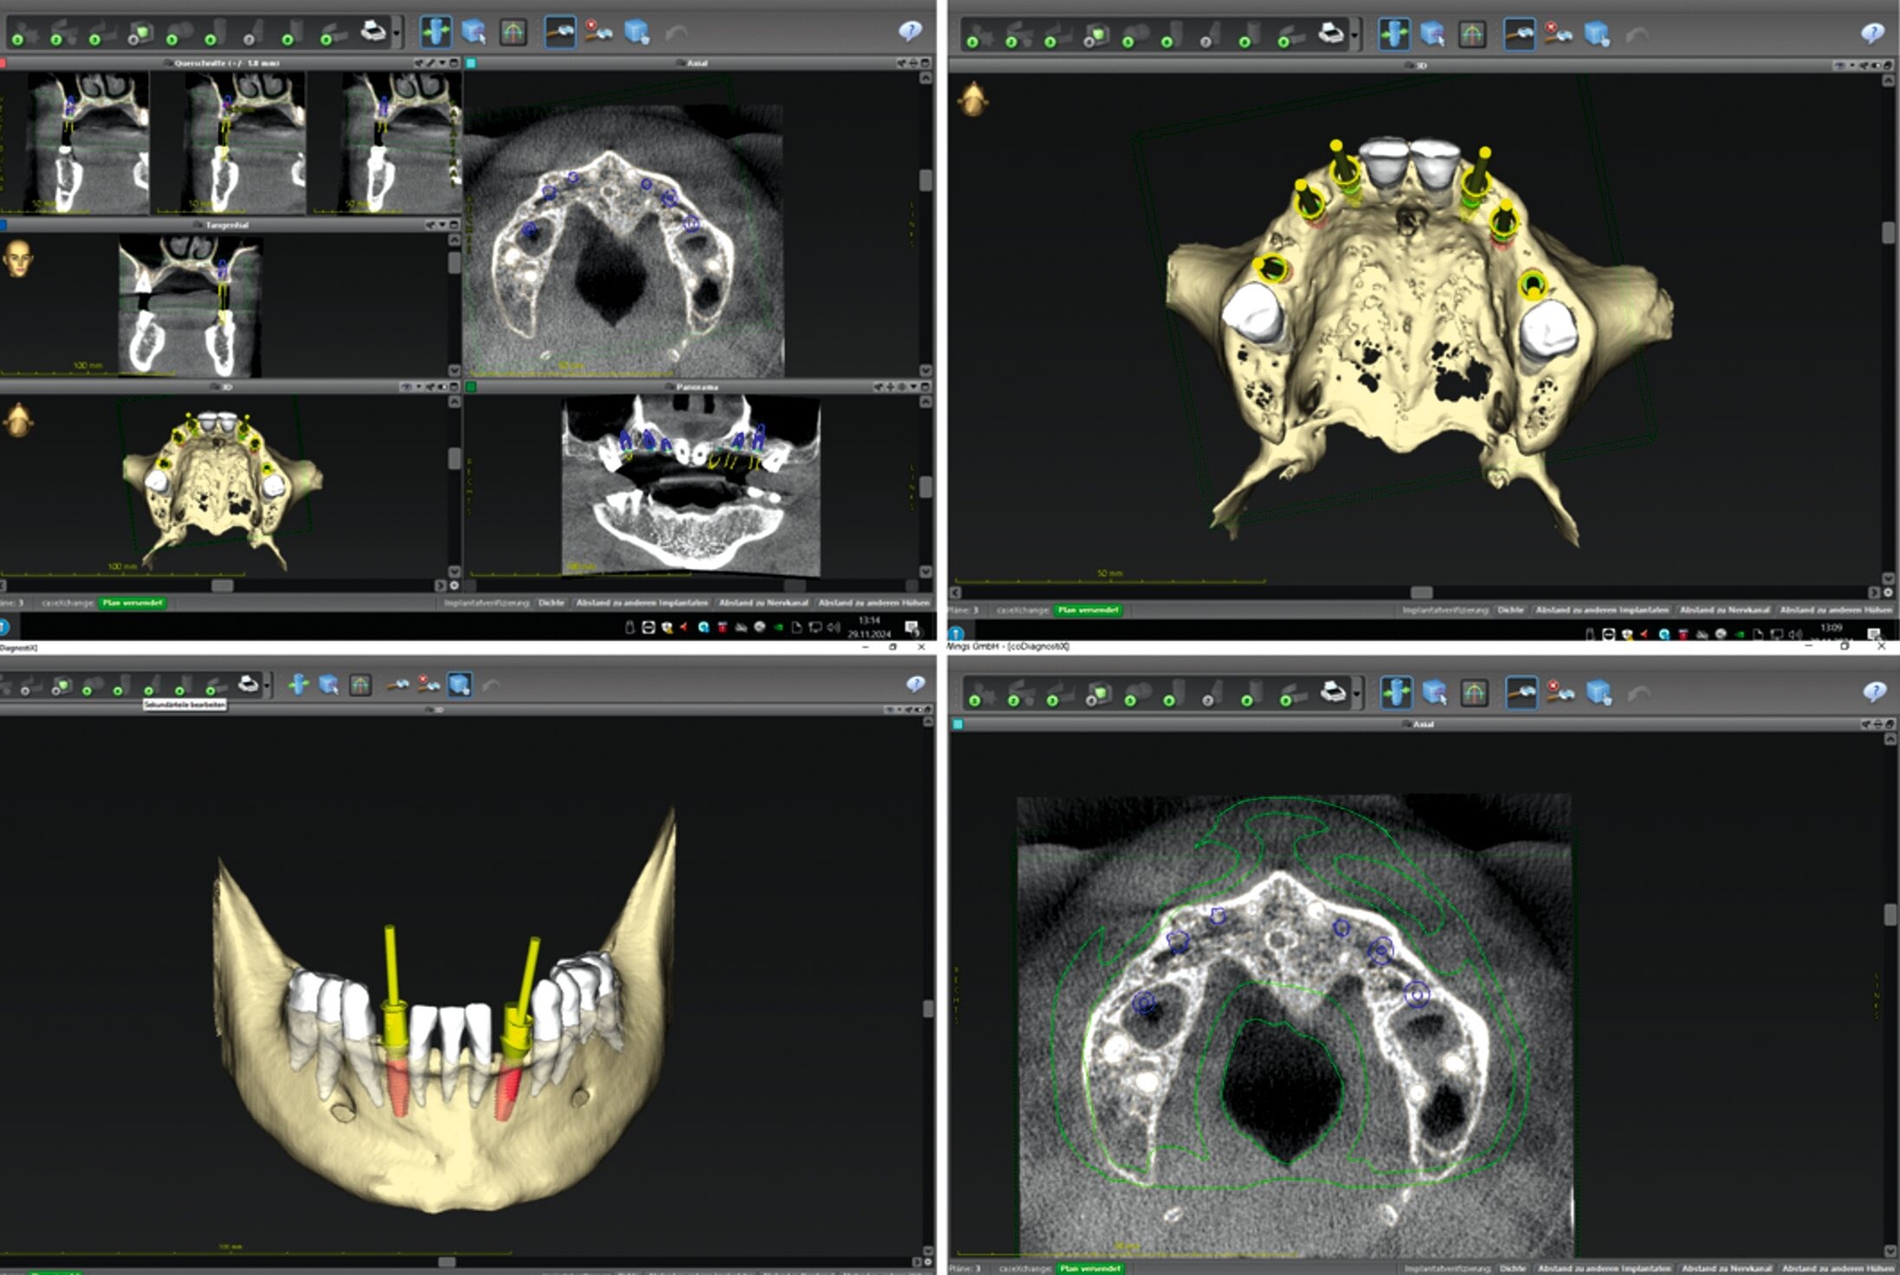

Zur Implantationsplanung wurden nach Abschluss der Vorbehandlungen und Prophylaxemaßnahmen zunächst eine digitale Volumentomografie (DVT) sowie aktuelle Situationsmodelle von Ober- und Unterkiefer zur Beurteilung der ossären Ausgangssituation erstellt. Es folgte die digitale Planung der Implantationen an den Regionen 12, 13, 13, 22, 23, 25, 33 und 43 (CoDiagnostiX Dental Wings, Straumann, Basel, Schweiz) sowie die Übertragung der dreidimensional geplanten Implantationen in gedruckte Bohrschablonen und die Festlegung von Art und Zeitpunkt erforderlicher Augmentationen (Abbildung 5).